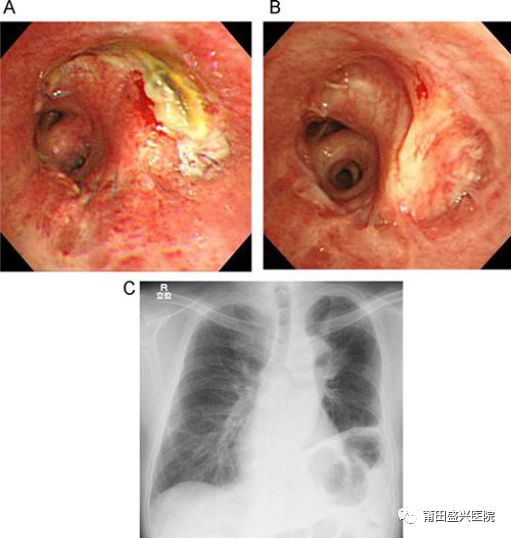

1、明確診斷:確定良噩性。肺癌患者多表現(xiàn)為肺部腫塊,大部分可通過(guò)CT等影像學(xué)檢查作出初步診斷,但也僅是影像學(xué)診斷,雖然多數(shù)情況下高水平放射科醫(yī)師的診斷與將來(lái)的病理診斷是相符的,但永遠(yuǎn)不能作為確診的金標(biāo)準(zhǔn)。為了能夠拿到細(xì)胞學(xué)或病理學(xué)的診斷,應(yīng)該常規(guī)行支氣管檢查,鏡下可進(jìn)行刷檢或組織活檢,達(dá)到真正的確診,從而根據(jù)病理診斷,進(jìn)行有效治療。

2、明確范圍。不是所有的肺癌通過(guò)影像學(xué)檢查就能明確病變的范圍,有些肺癌常沿支氣管壁浸潤(rùn),需要通過(guò)支氣管鏡檢查來(lái)直觀的了解病變真正侵犯到什么范圍,為手術(shù)切除范圍作出確切的判斷,避免切除過(guò)多或切除不夠。

3、有效治療。有些肺癌患者通過(guò)痰液細(xì)胞學(xué)已經(jīng)明確診斷,但也需要支氣管鏡檢查,可以進(jìn)行有效的治療,比如洗凈支氣管腔內(nèi)的痰液,清除管腔的脫落腫瘤等,都為手術(shù)打好基礎(chǔ),或?yàn)槠渌委熖峁└玫臈l件。